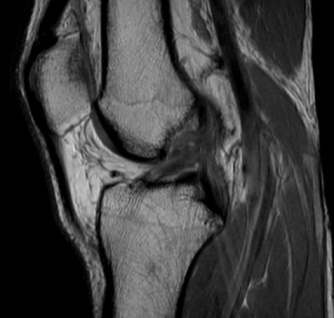

2) MRT-Aufnahme

Knie-MRT-Scan

MRT ist eine übliche Technik zur objektiven Diagnose eines VKB-Risses. An zweiter Stelle steht diese Beurteilungsmethode, da MRT-Befunde nicht hilfreich sind, um eine Knieinstabilität ein- oder auszuschließen. Das liegt vor allem daran, dass die Diagnose gestellt wird, während der Patient in einer Position verharrt, die es unmöglich macht, das Verhalten der Tibia im Vergleich zum Femur zu sehen.

Außerdem wird nach einer VKB-Verletzung Zeit benötigt, da die im Knie vorhandene Schwellung die Diagnose des Zustands des VKB erschwert. Diese Problematik ist das Ergebnis des Blutes, das das VKB umgibt.

Dennoch sollte beachtet werden, dass die Behandlung von VKB-Verletzungen wesentlich von der genauen Diagnose anderer umliegender Bandstrukturen des Knies abhängt, insbesondere des lateralen Kollateralbandes (LCL), des hinteren Kreuzbandes (PCL) und des Meniskus. Diese Strukturen können in der Tat mit Hilfe von MRT-Scans beurteilt werden, was diese Bewertungstechnik bei der Behandlung von Patienten mit VKB-Verletzungen immer noch sehr wertvoll macht.

Patienten mit kombinierten LCL/VKB- oder HKB/VKB-Rissen weisen in der Tat tiefgreifende Instabilitäten auf, die ein technisch anspruchsvolleres chirurgisches Verfahren erfordern, was, wenn es nicht berücksichtigt wird, das VKB-Transplantat zu einem höheren Risiko des Kollapses prädisponiert.